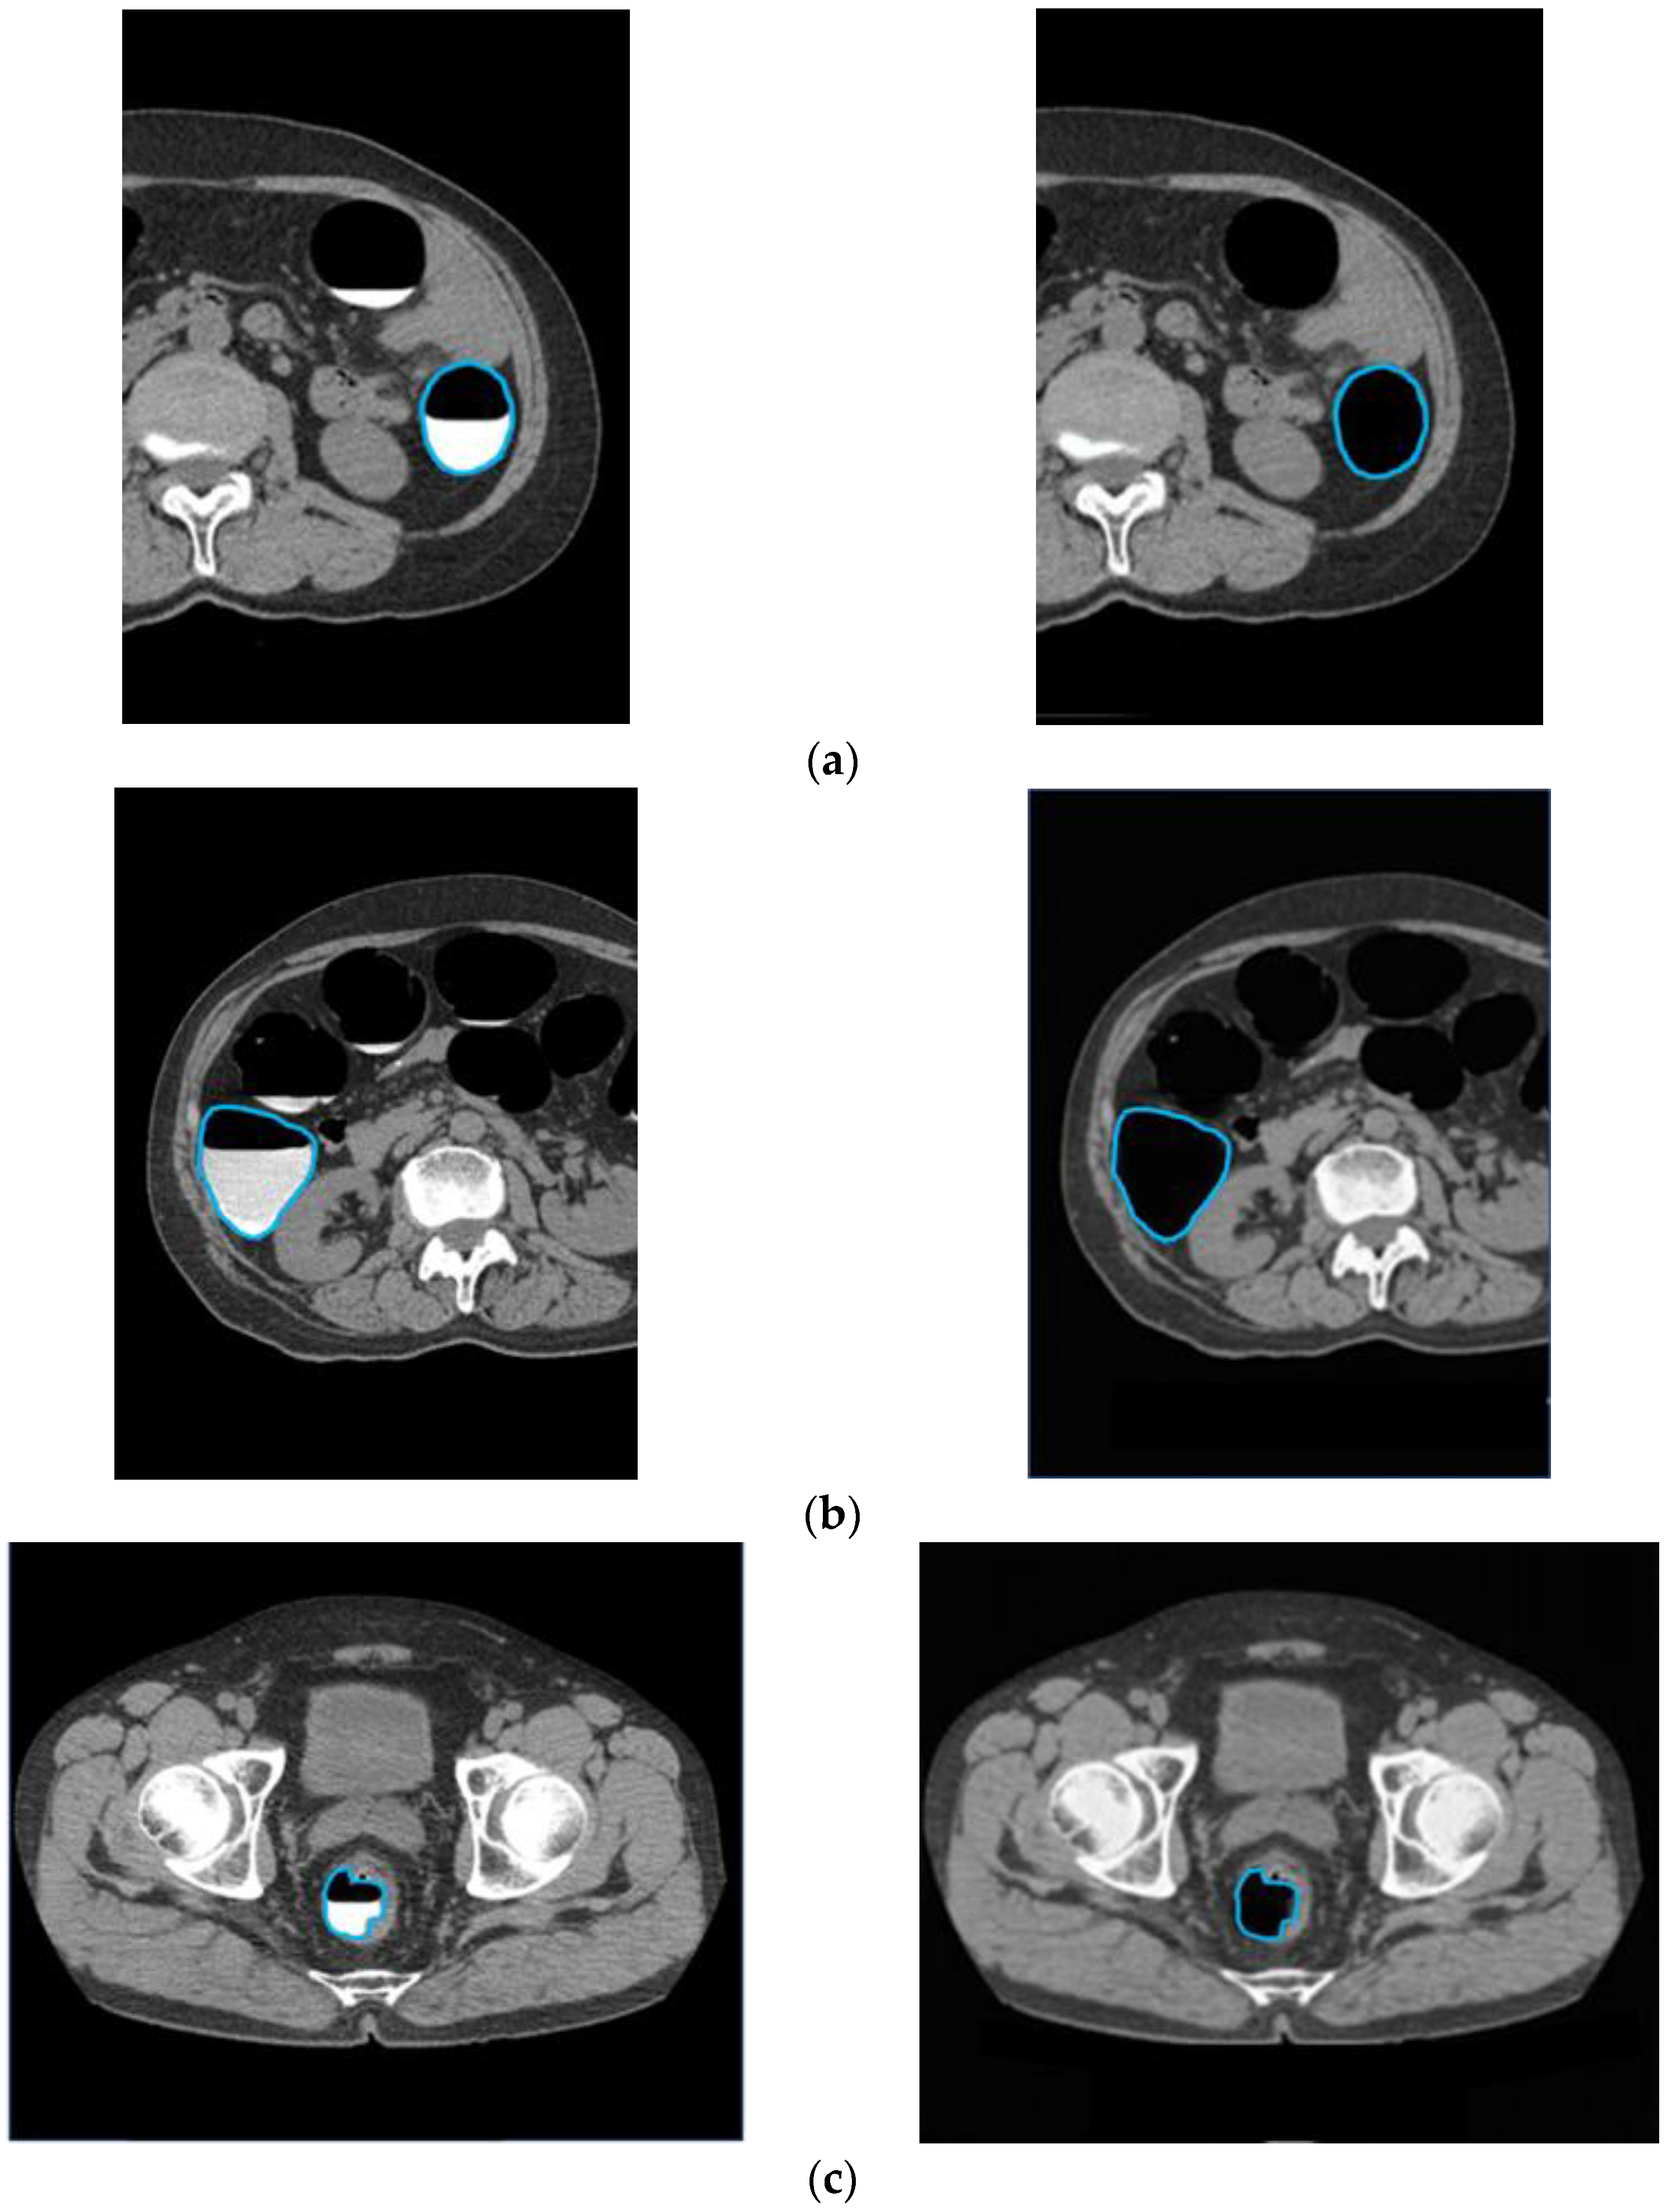

3.1. Cleansing Images Generated Using CycleGAN

4.1. Images Generated by CycleGAN